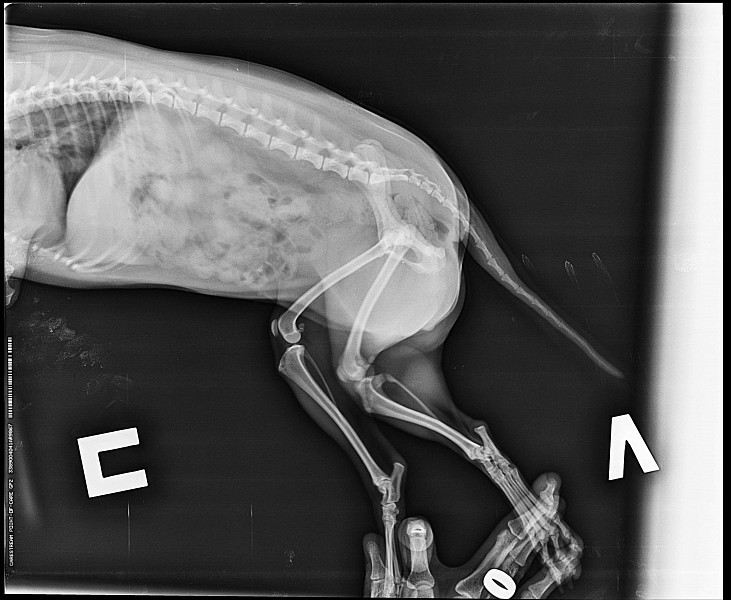

Рентгеновские снимки перелома лапы у кота: диагностика и лечение